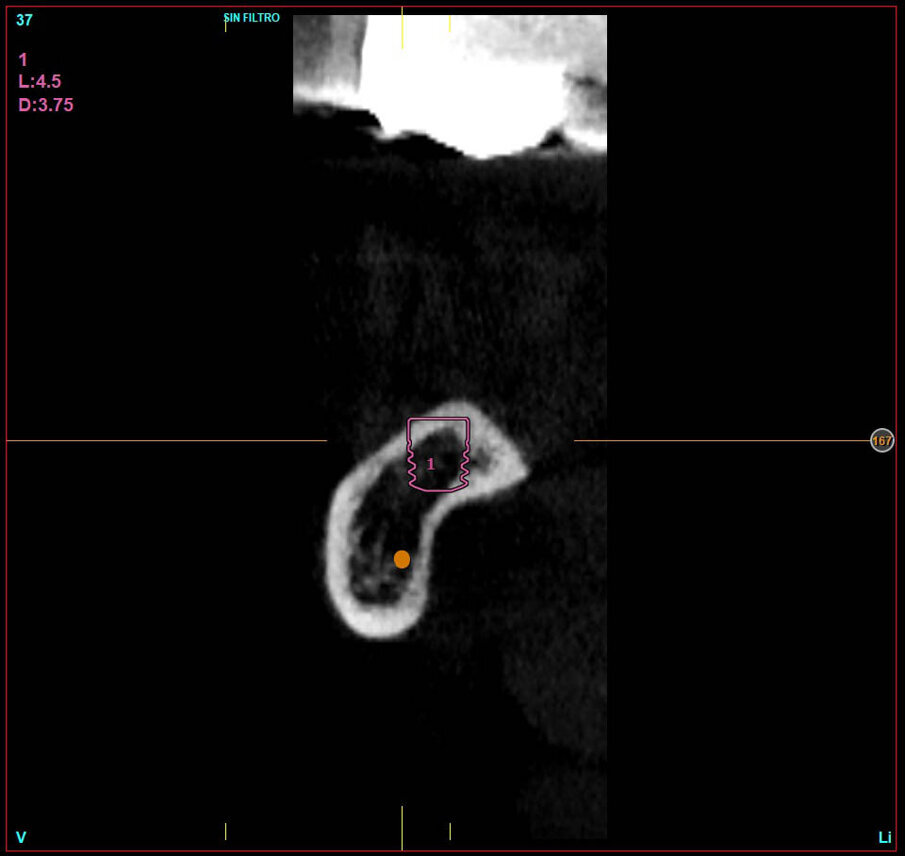

Dopo l’esecuzione di esame CBCT della zona (Figg. 3, 4), si evidenziò che la quantità d’osso al di sopra del nervo alveolare era esigua e inoltre la mandibola presentava un grosso sottosquadro. Si pianificò l’inserimento di due impianti dentali BTI CORE da 4,5 mm di lunghezza e 3,75 mm di larghezza.